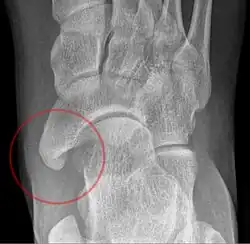

Radiological images

• Type 3: A cornuate navicular bone represents an enlarged navicular tuberosity, which may represent a fused Type 2 accessory bone. Occasionally symptomatic due to bunion formation.